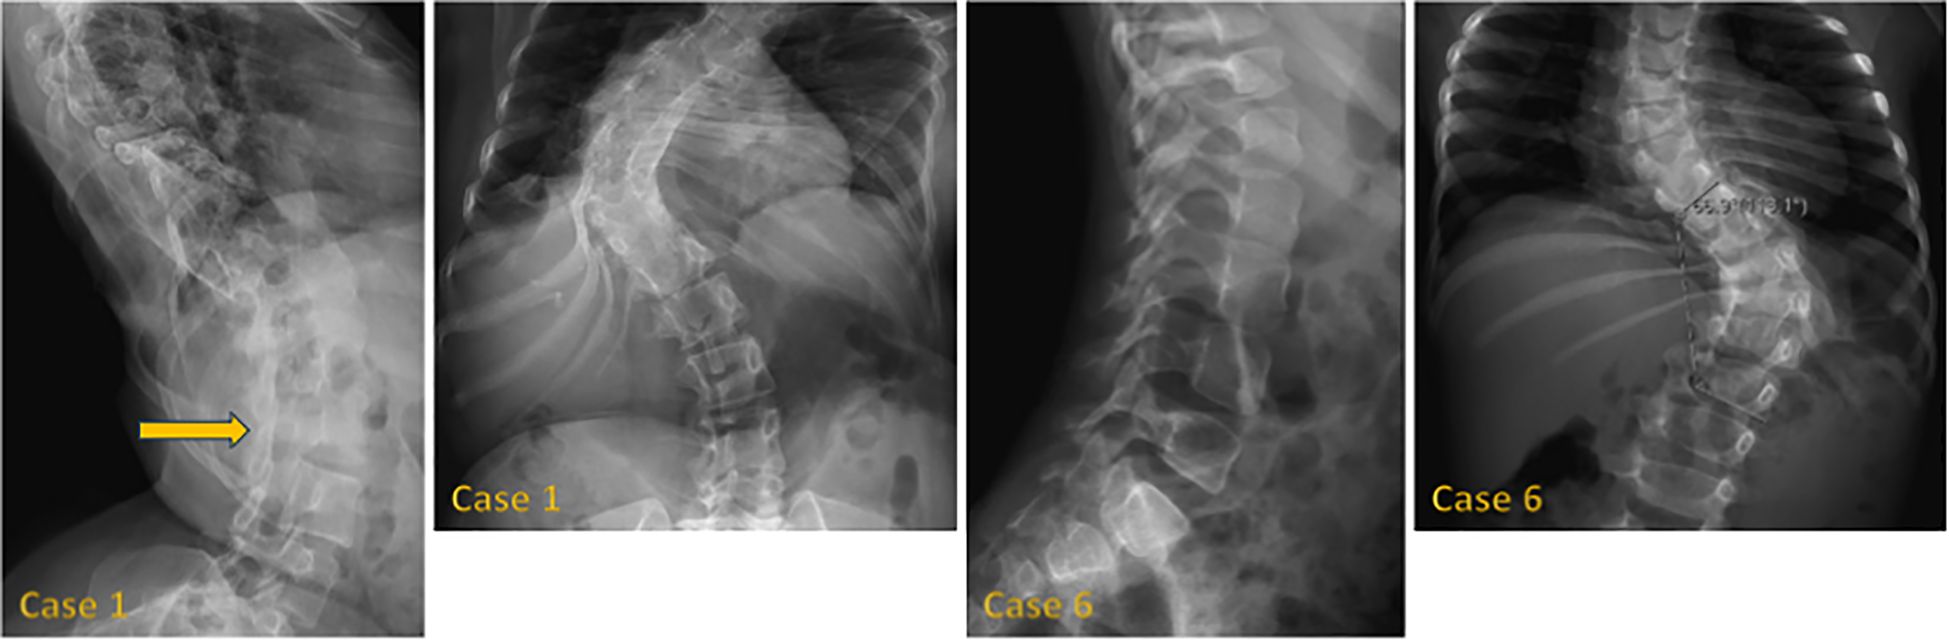

Background: 3M syndrome (3MS) is a very rare autosomal recessive disorder characterized by short stature, distinctive facial features, and skeletal abnormalities. The condition is frequently underdiagnosed due to its nonspecific symptoms and normal neurocognitive development. Few reports exist on its clinical course and response to growth hormone (GH) therapy. Therefore, this study aims to describe the clinical features of Saudi patients with 3MS and to investigate the effects of growth hormone therapy on growth. Methods: We conducted a retrospective case series of 14 Saudi patients from 11 families with genetically confirmed 3MS at King Faisal Specialist Hospital and Research Centre in Riyadh. Results: The mean age at diagnosis was 5.4 years. Consanguinity was present in 79% of cases. The most frequently affected gene was CUL7 (57% of cases), followed by OBSL1 and CCDC8. All variants were predominantly homozygous and classified as pathogenic or likely pathogenic. Clinical abnormalities included growth retardation, dental abnormalities, spinal abnormalities, and a This is a provisional file, not the final typeset article characteristic facial appearance. GH therapy was administered to 10 children; 5 demonstrated a measurable improvement in growth velocity, while 5 did not respond or discontinued treatment. IGF-1 was within/low-normal in most tested cases, with two elevated results. Conclusion: Our study highlights the extensive phenotypic variability of 3MS and underscores the predominantly autosomal recessive inheritance pattern in this population. GH therapy may provide a growth benefit in select cases, although resistance and poor response remain a challenge. Genetic testing is crucial for accurate diagnosis, individualized management, and appropriate family counseling.